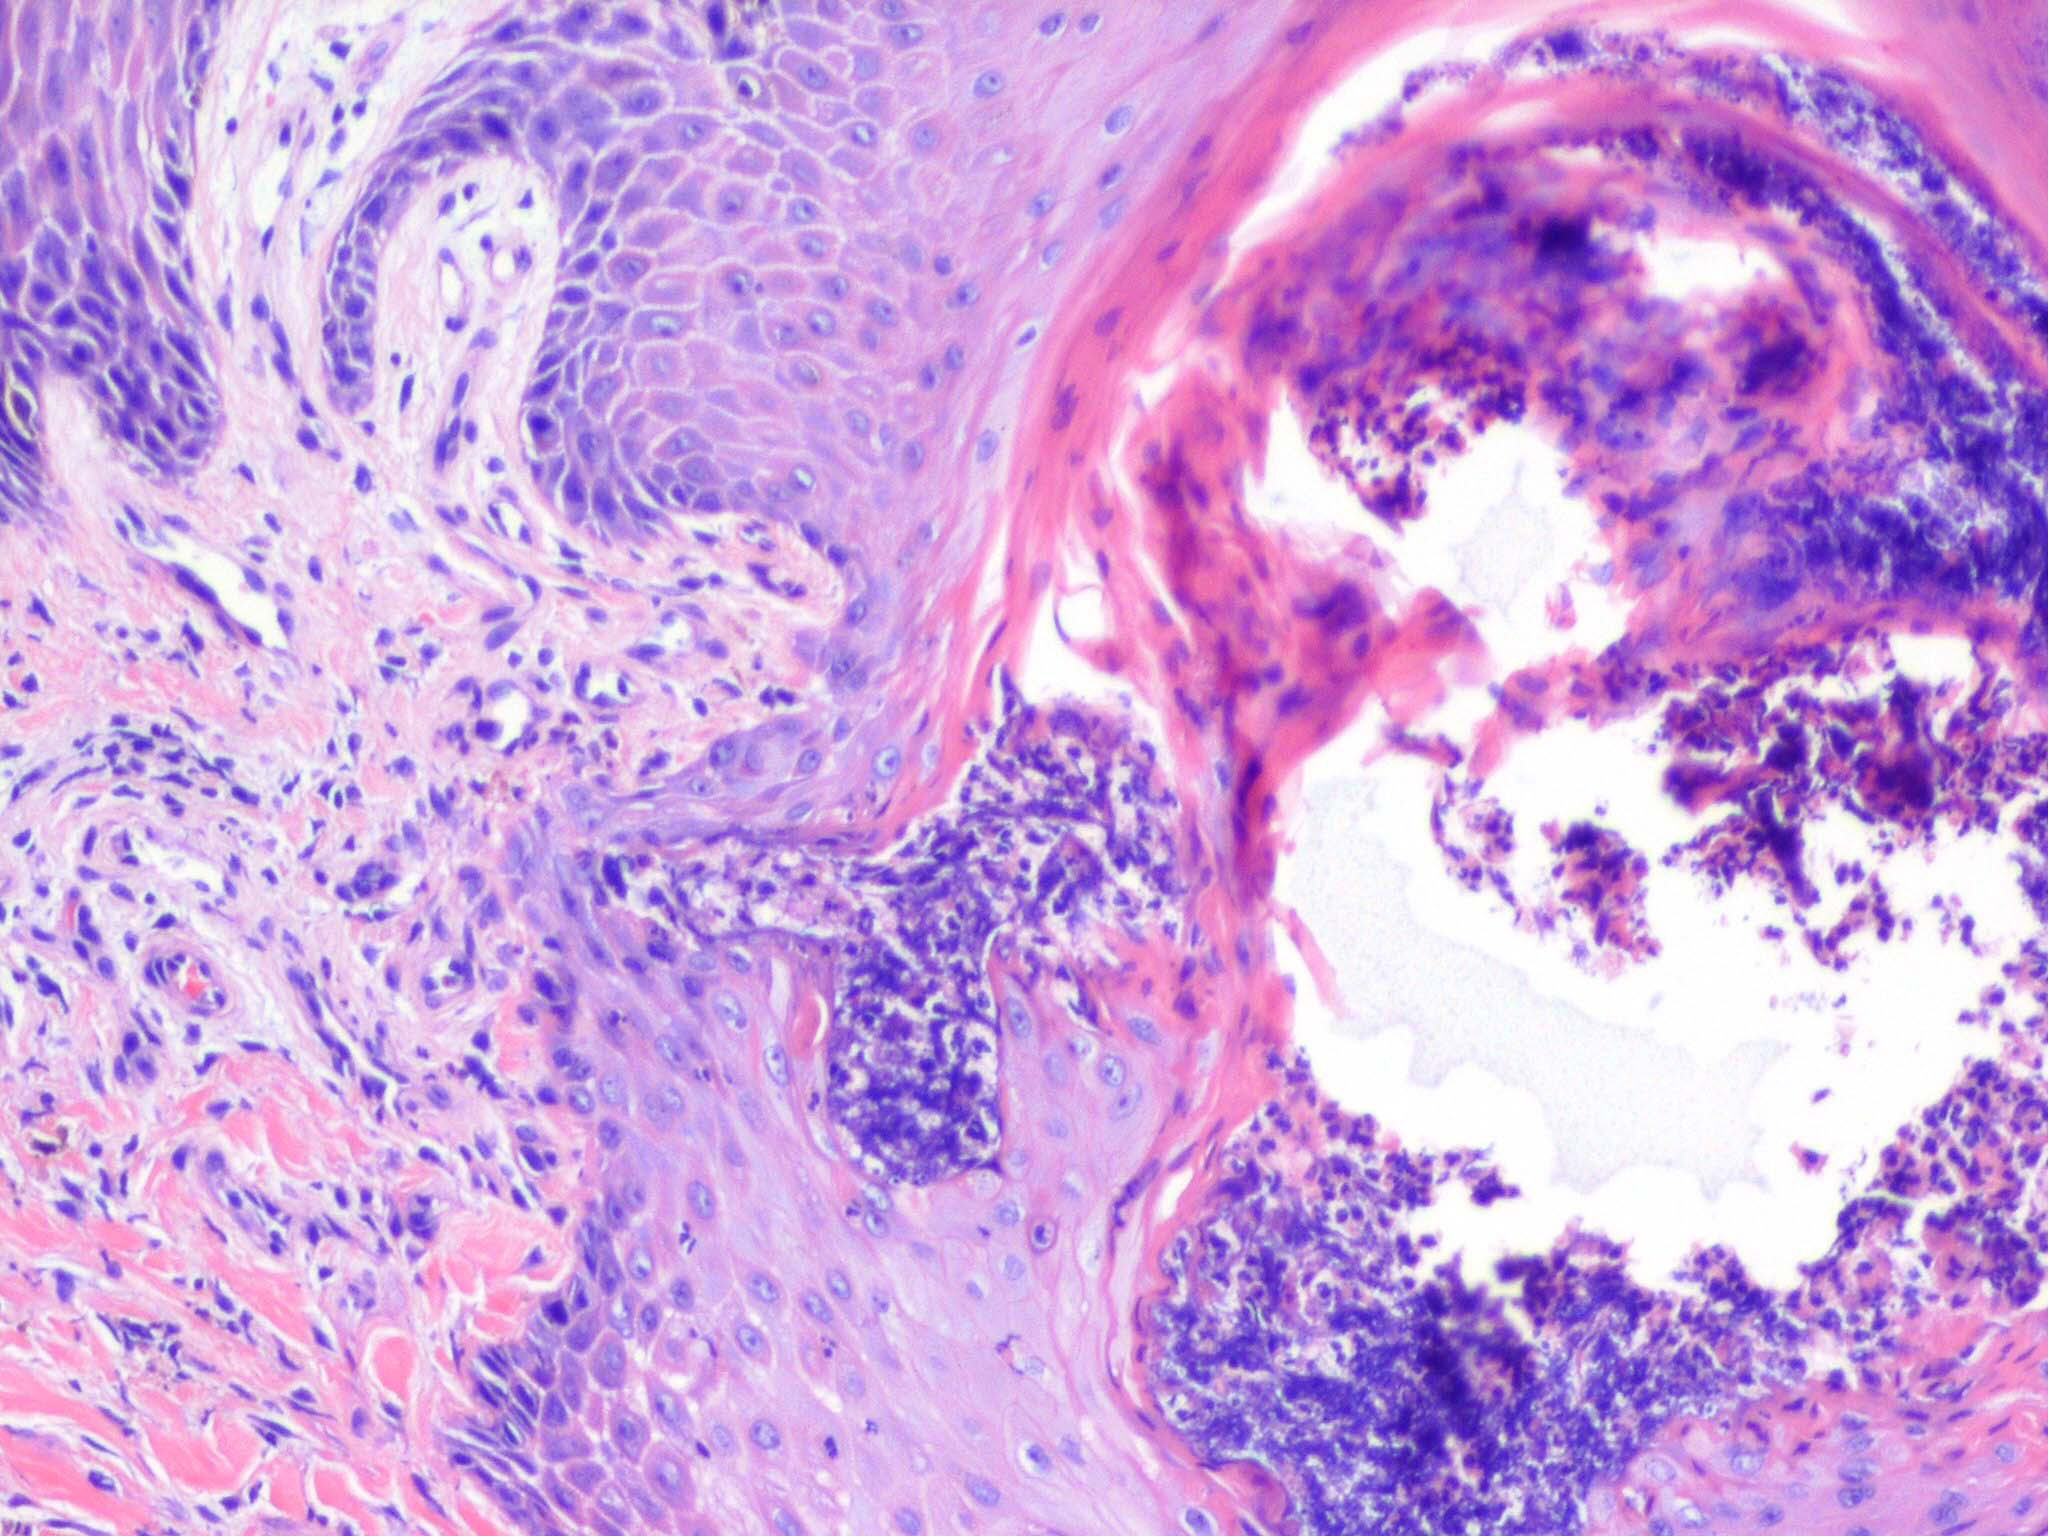

Acquired perforating dermatosis = الجلاد الثاقب المكتسب